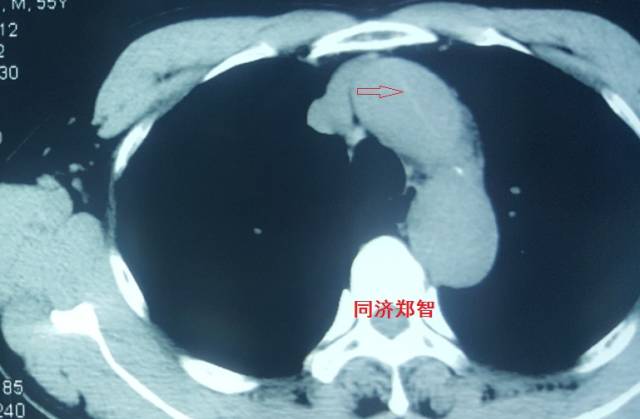

病例五

平扫CT提示主动脉弓层面及右肺动脉层面均可见主动脉血管腔内的内膜片影(红色箭头所示),CTA显示为A型主动脉夹层。

图8-11